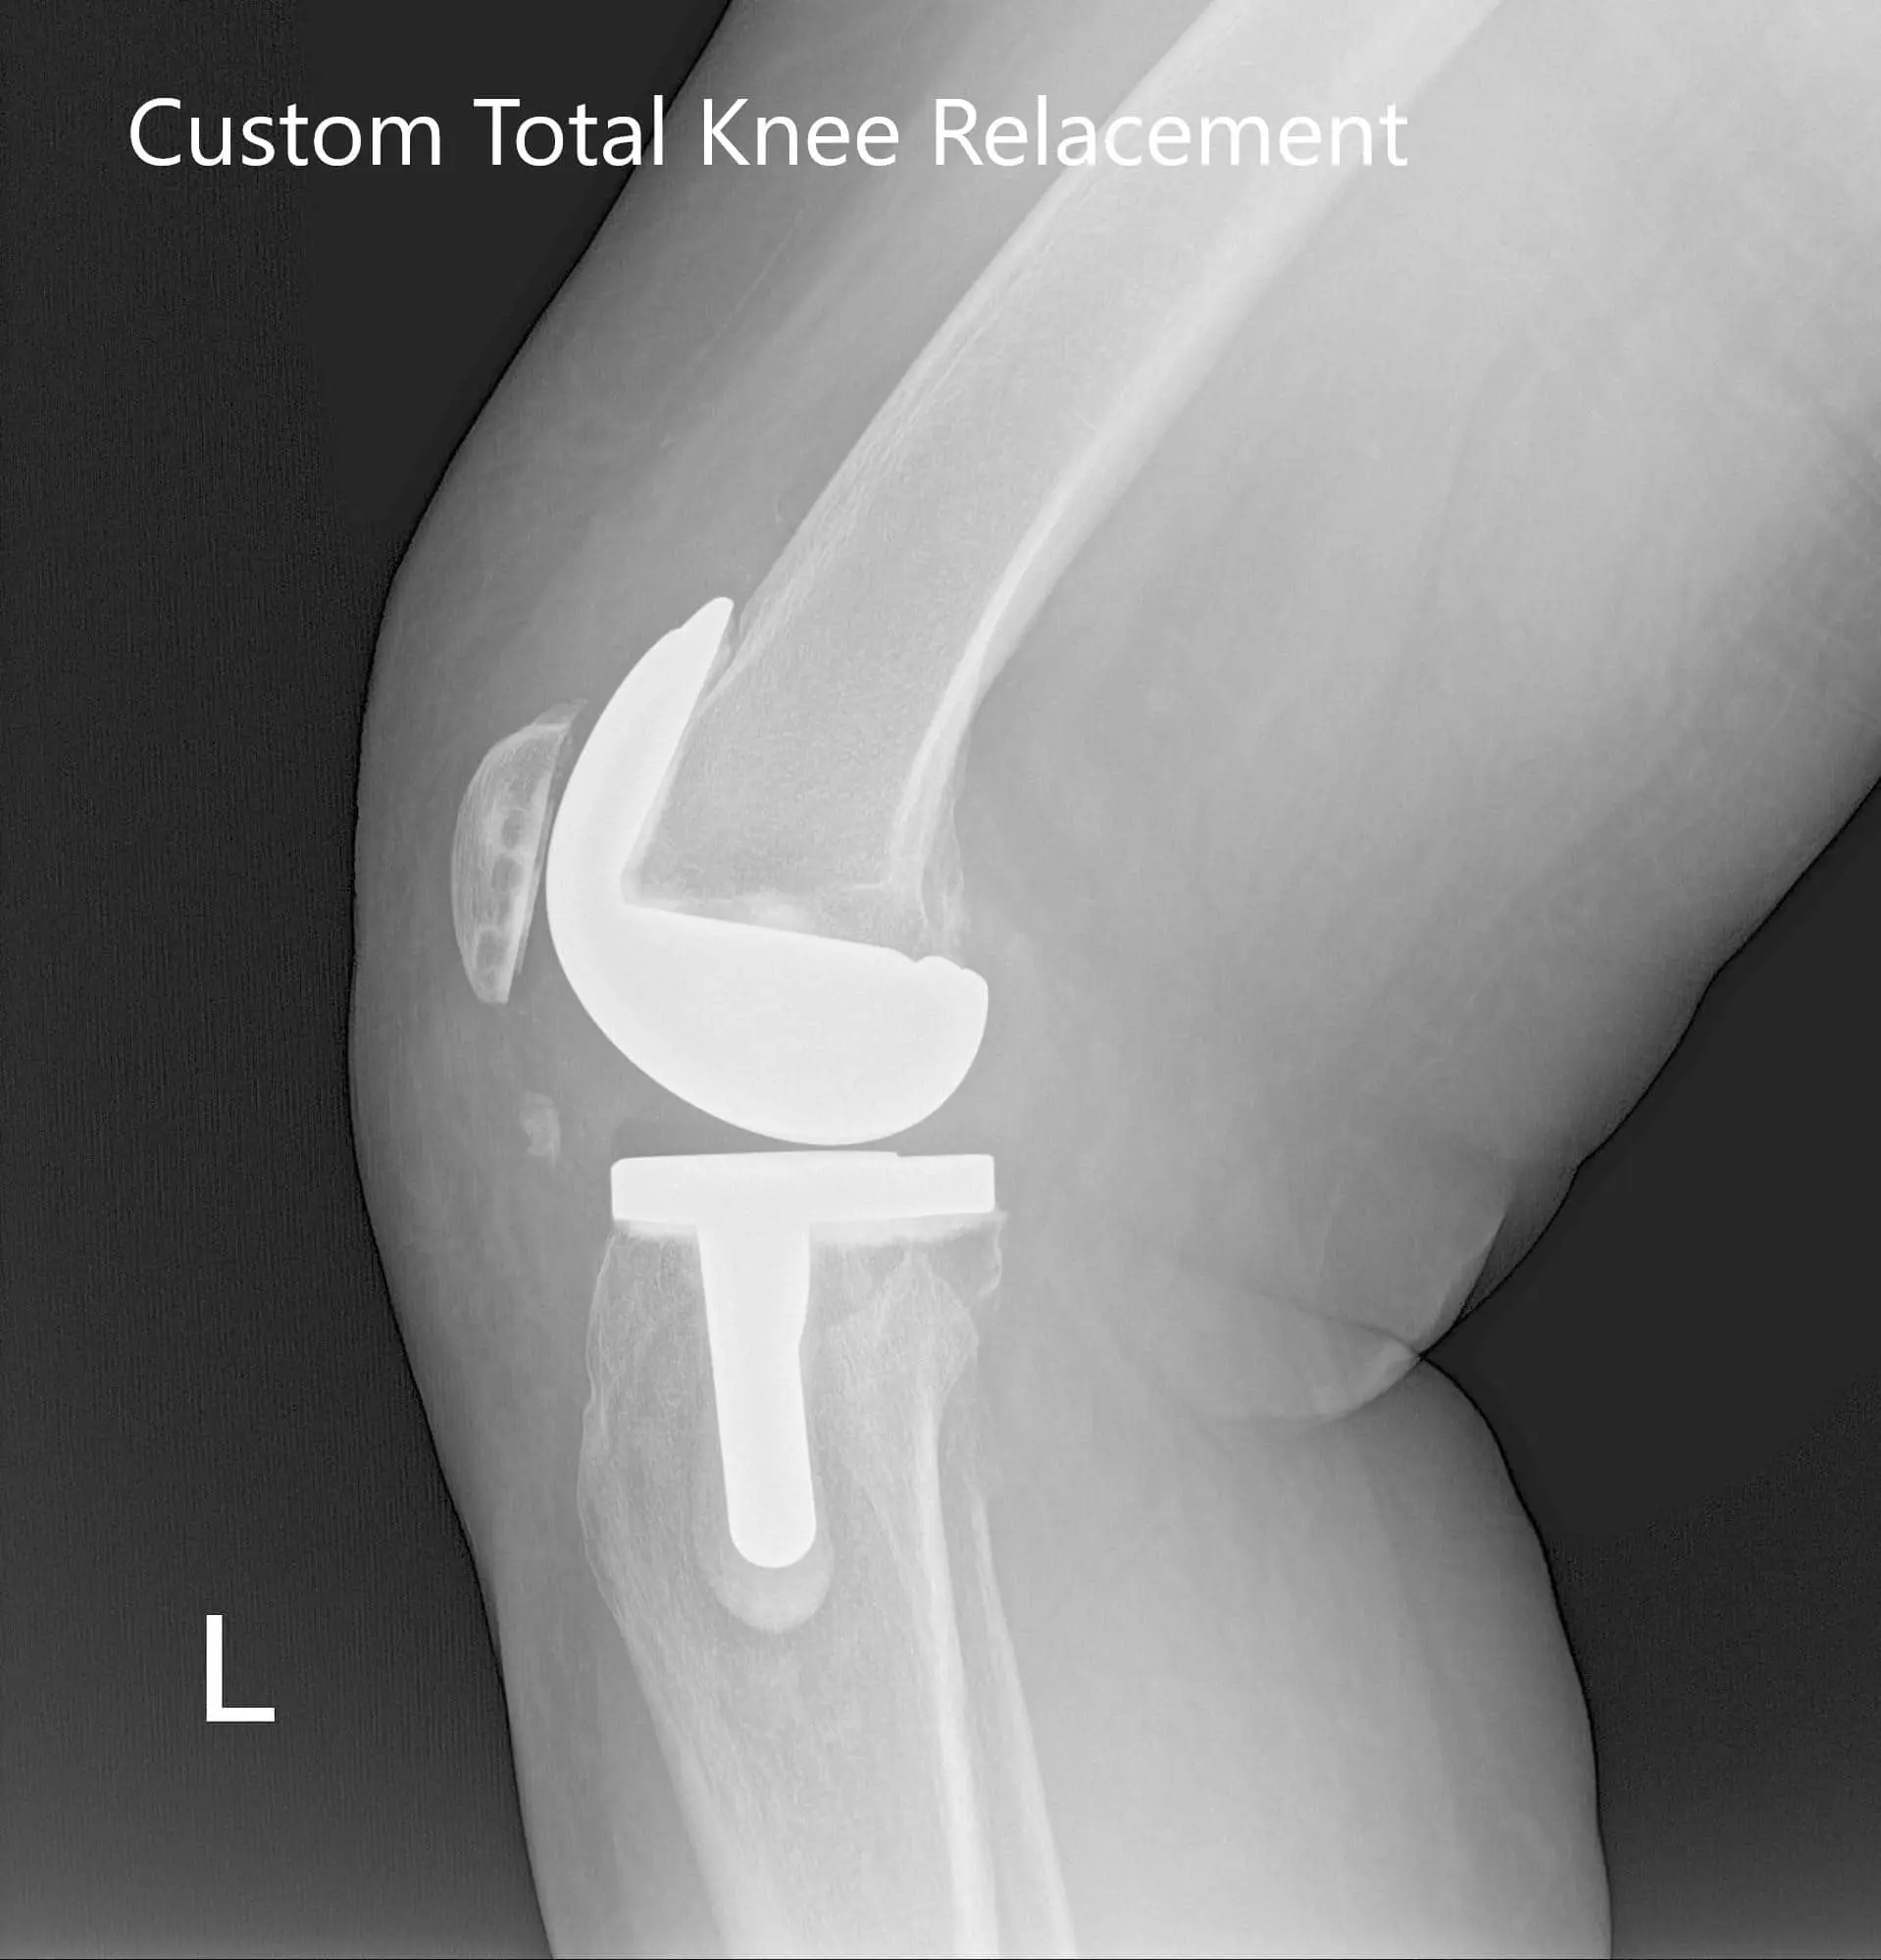

Implants used: 8 mm posterior stabilized polyethylene with tibial tray, femoral implant 32 mm, 6 mm thickness polyethylene with an 8 mm polyethylene insert.

Post Operative X-Ray of the left knee showing AP and lateral viewPost Operative X-Ray of the left knee showing AP and lateral view - img 2

Post Operative X-Ray of the left knee showing AP and lateral view